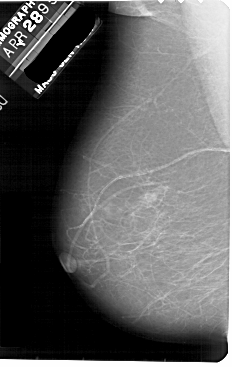

A_1881_1.RIGHT_MLO

RIGHT_MLO LINES 5491 PIXELS_PER_LINE 3256 BITS_PER_PIXEL 12 RESOLUTION 43.5 OVERLAY